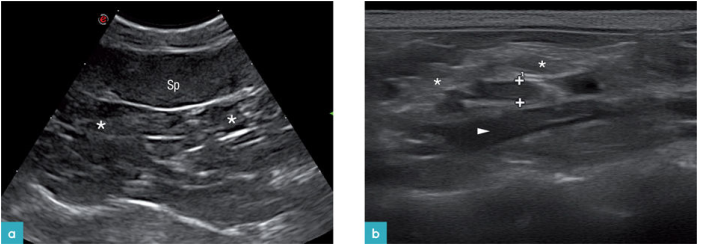

腹膜壁层在近场上呈现一条高回声亮线(图1)。器官表面的腹壁脏层又称为浆膜层,包裹在肠道外壁,胃的外壁,膀胱的外壁,脾脏和肝脏的外壁,也呈高回声的亮线(图2)。腹膜结缔组织连接腹腔各个器官,有3个双层腹膜结构,分布是网膜,肠系膜,韧带(图3)猫的镰状韧带位于肝的腹侧被脂肪组织所包裹,相较于肝脏实质的回声镰状韧带可呈无回声或低回声,偶尔呈高回声,它的质地更加粗糙些(图4)。肝脏包膜的高回声亮线是镰状韧带和肝脏实质的分界。而猫的分界线比较模糊,没有经验医生很难将镰状韧带和肝脏实质区分开。可能会将镰状韧带误认为是肝脏,在进行细针抽吸时吸出的不是肝脏组织而是脂肪。

腹部器官的血供是从主动脉的分支而来(下腹动脉,前肠系膜动脉,肾动脉,旋髂深动脉,髂外动脉,髂内动脉,骶中动脉)。腹腔的静脉血液有两个走向,一个走向是汇入后腔静脉,另一个走向是汇入门静脉。测量主动脉和CVC的血流速度时,需要使探头的切面与腰椎的长轴平行。腹主动脉从膈下行到第六腰椎的水平面,位置稍稍偏中线的左侧,是有高回声的管壁,内部是无回声的液体(图9a和9b),横截面上会更加清晰。二维扫查可以见到主动脉所有的分支。后腔静脉位于腹主动脉的右侧在超声形态上与腹主动脉相似。后腔静脉较腹主动脉而言,更容易被探头压扁(图9c)。门静脉位于肝门,它的分支有胃十二指肠静脉,脾静脉,前肠系膜静脉和后肠系膜静脉。门静脉位于腹中线偏右(图9d)。